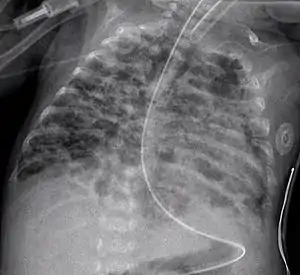

Chest film showing increased opacity in both lungs, indicative of pneumonia